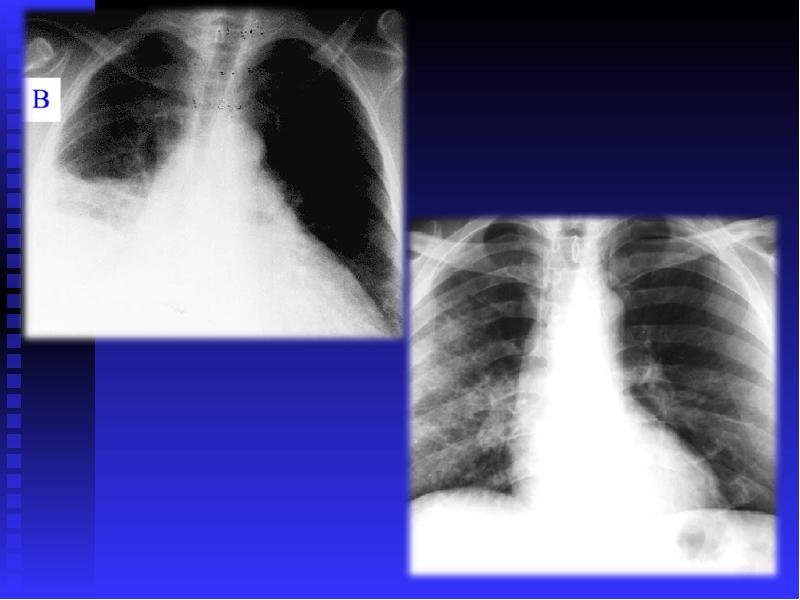

Медицинская тема: легочные осложнения при пневмонии